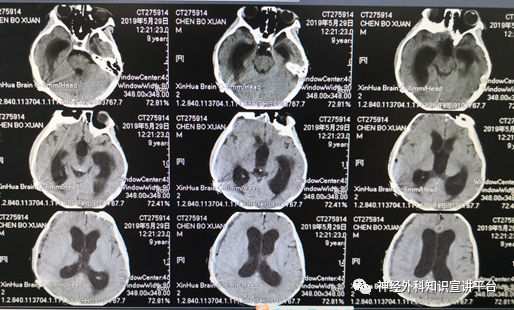

患者出现急性脑积水,GCS评分6分,调压至50mm水柱,查CT示脑积水进一步加重,颞角扩大更加明显。

穿刺分流阀提示脑压仅50mm水柱,但脑积水无法缓解

穿刺分流阀,缓慢抽液100ml。

穿刺分流阀抽液及低位放液有效

1小时后,患者意识情况好转, GCS评分9分,3小时后GCS评分11分,可少量饮水。